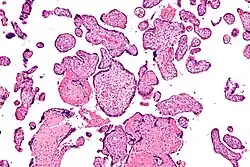

![]() Micrografía de vilitis de etiología desconocida. Tinción H&E. | ||

Histomorfológicamente, la VUE se caracteriza por un infiltrado linfocitario de las vellosidades coriónicas sin una causa demostrable. Las células plasmáticas deben estar ausentes; la presencia de células plasmáticas sugiere una etiología infecciosa, por ejemplo, infección por CMV.